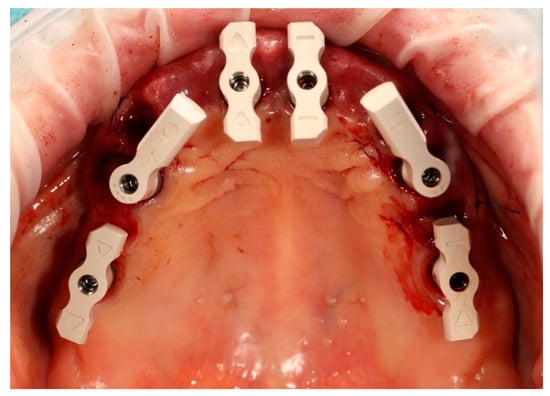

Figure 4. Multi-unit abutments secured onto all six supporting implants, including the newly placed implants at positions 14 and 24, following removal of the existing restorations.

Simultaneously, the existing implant-supported crowns in positions 16 and 26, as well as the anterior implant-supported bridge, were unscrewed from the supporting implants. Multi-unit abutments were then selected and secured onto all six supporting implants, including the newly placed implants at sites 14 and 24 (Figure 4).